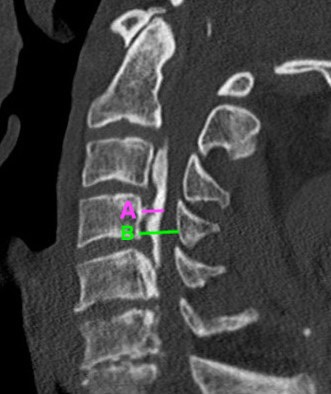

CT

OPLL Cervical SpineOPLL 2

OPLL on CT

Occupancy ratio